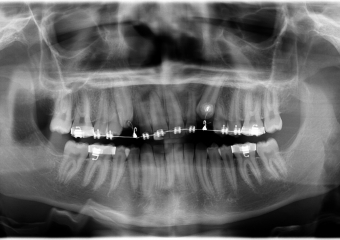

Rx Panoramico - Tracionamento finalizado - Clínica Cliniface

Rx Panoramico - Tracionamento finalizado